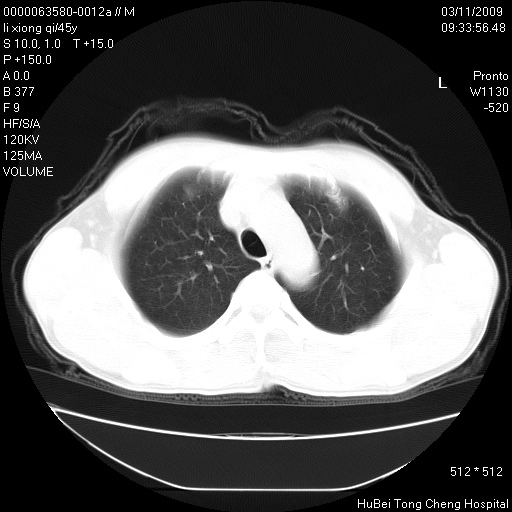

患者 男,45岁。胸痛,咳嗽伴痰中带血1月余。

临床诊断:肺结核?

胸部ct轴位平扫(层厚10mm,螺距1.5,重建间隔10mm),图像如下:

考虑肝癌肺转移